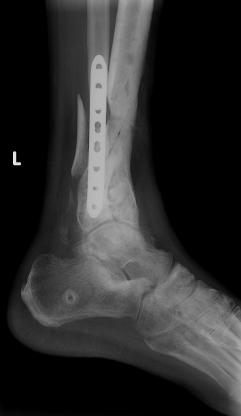

Postoperative (12th) images of left ankle

The images displayed here were created at various appointments following surgery performed by Dr. Daniel Saunders. In the X-Ray you can see

where Dr. Saunders has removed the fibula plate, joined the tibia and fibula with a screw, built-up the area of the tibia where previously

there was considerable absence of bone and lastly added the EBI OsteoGen-M Bone Stimulator (dual lead). The photos show the left side site

where the fibula plate was removed, the top site where donor bone, bone filler material and the stimulator were added and the right side

where the tissue has burst because of swelling. Liam was placed on an IV drip of Vancomycin following surgery to combat the potential onset

of Osteomyelitis. The image of the cast includes the fibula plate that was removed during surgery. The next images were taken later and show

that the staples and stitches were removed. In one of the images, you can see Liam's wife Madeline helping with leg cleanup and in one image

can be seen the EBI representative after being put to work (holding up the left leg while the latest cast cures) by Dr. Saunders. Later shots show

a healing tissue burst site with some overgrowth and Dr. Saunders cauterizing the overgrowth. Bones shifting too much (shown in X-Rays). The

last images are of the left ankle prior to the 13th surgery.